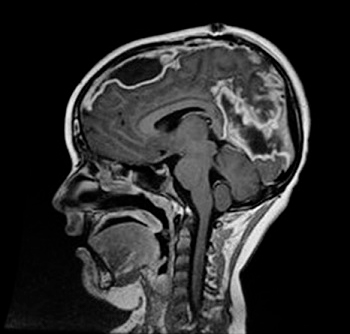

Caso 1. Niño de 8 años que ingresa por cuadro de sinusitis que no mejora a pesar de recibir antibioterapia por vía oral. Al cuarto día de tratamiento antibiótico intravenoso con amoxicilina-clavulánico, presenta crisis convulsivas generalizadas de breve duración. Se realiza una prueba de imagen que evidencia la presencia de empiema subdural y pansinusitis (Fig. 1). A la exploración, presenta Glasgow 15, leve hemiparesia izquierda y sensación de hiperestesia en la pierna del mismo lado. Se inicia tratamiento con cefotaxima, vancomicina y metronidazol y se realiza drenaje del empiema frontal mediante craneotomía, sin incidencias postoperatorias. Recibe tratamiento con gabapentina y levetiracetam, con el que mejora su dolor neuropático y se resuelven las crisis convulsivas. A los 10 días de la primera intervención, comienza con fiebre y disminución del nivel de conciencia, por lo que, ante el evidente empeoramiento clínico y radiológico (Fig. 2), se realiza segunda intervención quirúrgica con ampliación de la craneotomía inicial y drenaje interhemisférico del empiema y se sustituye el tratamiento con cefotaxima por meropenem en perfusión extendida. Se cultiva el material purulento drenado y se aísla Streptococcus intermedius. Tras cumplimentar seis semanas de tratamiento antibiótico intravenoso y tras objetivar mejoría de la imagen radiológica, el paciente es dado de alta sin secuelas, a excepción de una ligera paresia de la extremidad inferior izquierda evidenciada con la marcha autónoma.